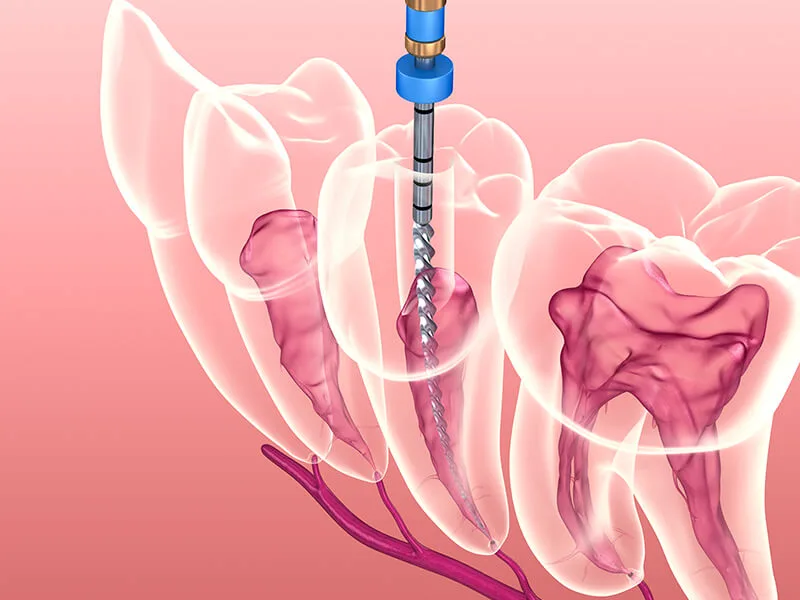

Abordagens Eficazes para o Abscessos Dentários Tratamento

As intervenções para o abscessos dentários tratamento variam conforme a gravidade e a origem da infecção. É essencial contar com auxílio profissional para determinar qual técnica trará o melhor resultado para cada caso.

Existem opções terapêuticas que possibilitam o alívio imediato da dor enquanto eliminam o foco infeccioso. O acompanhamento rigoroso assegura que a recuperação ocorra sem intercorrências.